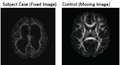

- Fiber geometry based registration with Lauren Donnell. Figures before and after registration attached on top of page.